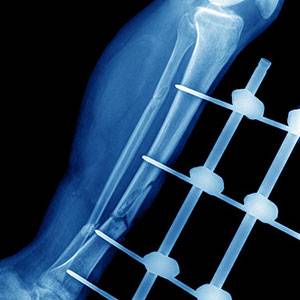

Рентгенологическая картина зависит от формы ложного сустава. При латентный формах большеберцовая кость углообразно искривлена, отмечаются явления склероза, однако чаще здесь определяются кистозные полости. При фиксированных формах четко представлены щель между фрагментами, явления склероза или кистозного рассасывания фрагмента ложного сустава, концы их, как правило, истончены (Дмитриев М.Л., Баиров Г.А., Терновой К.С., Прокопова Л.В., 1974). Малоберцовая кость удлинена или углообразно изогнута. Концы костных фрагментов области ложного сустава истончены, имеют вид «сосулек». На этом же уровне, как правило, определяется ложный сустав малоберцовой кости. Периферический фрагмент малоберцовой кости в таких случаях нередко расположен параллельно костям стопы, резко представлен остеопороз.

С.А.Рейнберг (1955) следующим образом описывает рентгенологическую картина врожденного псевдартроза, которая весьма разнообразна: «Патологических процесс локализуется в диафизе длинной трубчатой кости, в огромном большинстве случаев в большеберцовой кости. Вначале диафиз показывает только общие признаки недоразвития, некоторую степень атрофии, и только в большей или меньшей степени кость бывает искривлена. Если учесть это искривление, то в большинстве случаев обнаруживается и некоторое общее удлинение большеберцовой кости. В корковом веществе под надкостницей появляется довольно хорошо ограниченное овальное кистовидное просветление или же несколько рядом расположенных подобных участков. Затем на уровне поражения наступает либо рассасывание костной ткани с заострением диафизарных фрагментов, либо надлом или полный перелом патологического характера. Перелом не заживает, никогда не бывает следов костной мозоли. Процесс завершается образование ложного сустава, который имеет ряд отличительных для этого заболевания черт: развивается замыкающая пластинка, закрывающая костномозговую полость костных фрагментов – это картина обычная; но костные концы не моделируются в виде суставной головки и впадины, как это имеет место обычно, а истончаются, вытягиваются в длину и заостряются. Это напоминает картину, хорошо известную при перестройке костей на нервнотрофической почве. Иногда заостренные концы не соприкасаются друг с другом. Имеется патологическая подвижность, и перегиб постепенно нарастает. Такая рентгенологическая картина дает возможность лучше понимать сущность этой болезни и прежде всего подвергнуть критике общепринятое название. Истинного ложного сустава здесь нет, во всяком случае в первых стадиях развития врожденного порока. Псевдартроза нет и впоследствии – обычный ложный сустав со всеми его обязательными структурными элементами не образуется вовсе или только в редких случаях, как самая последняя фаза далеко зашедшего патологического процесса. Таким образом, так называемый врожденный псевдартроз не сущность болезни, а один из возможных исходов. Гистологически между фрагментами имеется только фиброзная связь, суставная щель отсутствует, равно как и хрящевая ткань далеко не всегда развивается при этой деформации. Нам кажется наиболее вероятным предположение, что так называемый врожденный псевдартроз есть результат внутриутробной перестройки костной ткани, вероятно, нервнотрофической природы.»